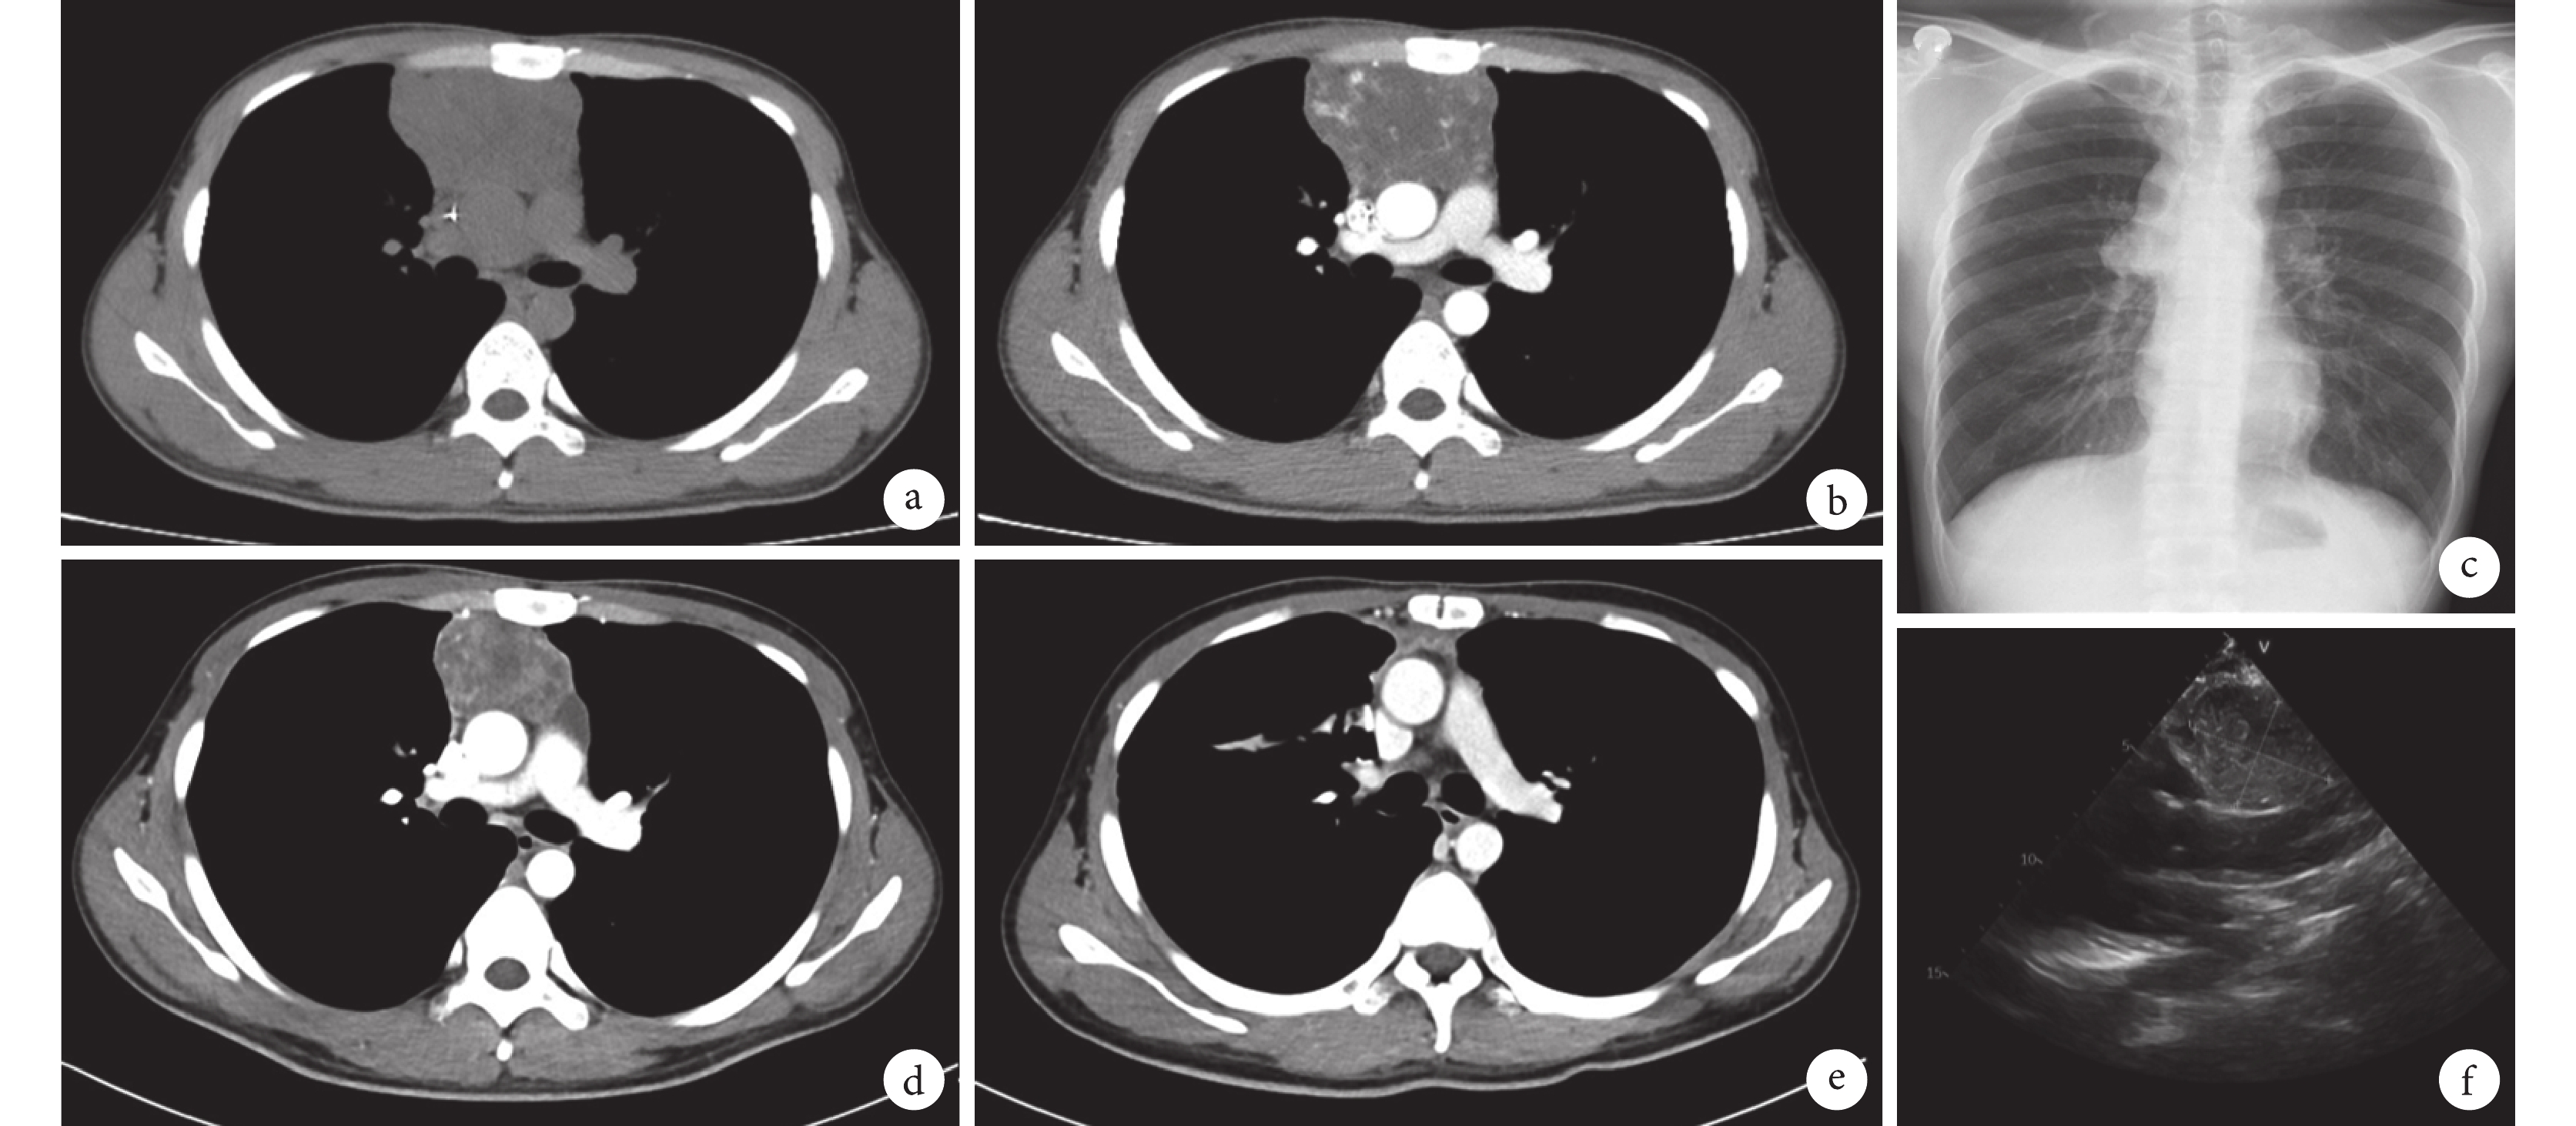

所有患者腫瘤均為單發,中位腫瘤直徑10.5(4.0,30.0)cm。17例位于前縱隔,其中5例累及中縱隔或全縱隔;1例位于后縱隔。CT影像表現:縱隔腫物,邊界清晰或欠清晰,常與周圍組織關系緊密;增強CT可見內部不均勻強化,與周圍血管界限欠清晰,大者可伴有鈣化灶或無強化囊性壞死區;腫物可侵入鄰近肺組織(10/18,55.6%)、心包(3/18,16.7%),甚至壓迫周圍靜脈(3/18,16.7%)及單/雙側支氣管(3/18,16.7%);少數病例可出現胸腔積液(1/18,5.6%);見圖1。

a:胸部平掃CT可見前縱隔軟組織占位,形態不規則,CT值10~37.9 HU,大小約7.9 cm×4.6 cm;b:胸部增強CT 可見前縱隔腫物不均勻強化,邊緣少許囊性成分,后緣與大血管緊貼;c:胸部X 線片可見右肺門軟組織影;d:化療后胸部CT 可見前縱隔軟組織占位較治療前明顯縮小,大小約5.0 cm×3.9 cm;e:術后胸部CT 可見原前上縱隔腫物已切除;f:心臟超聲圖像可見右心房外回聲不規則占位,大小約4.9 cm×3.7 cm